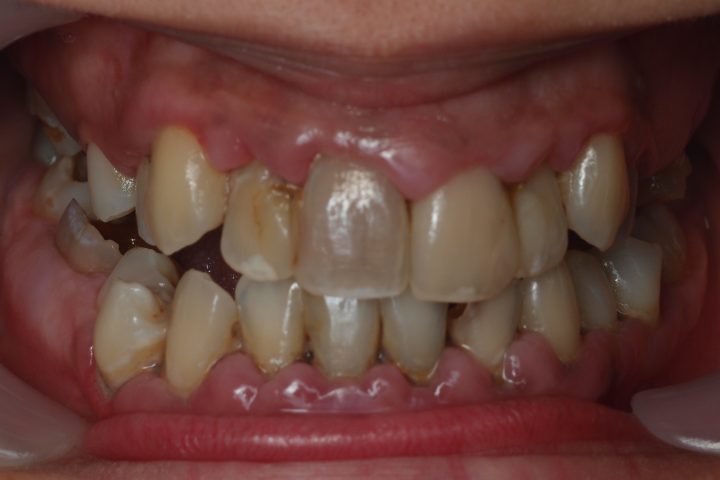

Clive kam aus England, und war im Jahr 2016 bei uns. Früher war er Berufsboxer, deswegen hatte er abgehärmte Zähne. Bis seinem 50. Geburtstag hat er sehr viele Zähne verloren, und die übrigen waren abgebrochen und verfärbt.

Er hatte 10 Tage lange Behandlung in der Zahnklinik Centrocc Dental. Sein Traum wurde erfüllt, Frau Dr. Erdélyi hat ihm schneeweißes, ausgezeichnetes Lächeln mit der Hilfe von 18 Stück Metallkeramik Kronen gezaubert.